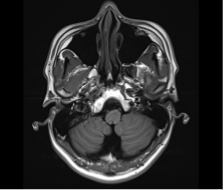

그림18.png 촬영 일시: 2025.05.17

<Fig 1. 정상 소견의 뇌 MRI>

다행히 MRI 영상을 확인해보니

뇌에는 특별한 이상이 없었어요.

정말 안도의 한숨이 나왔죠.